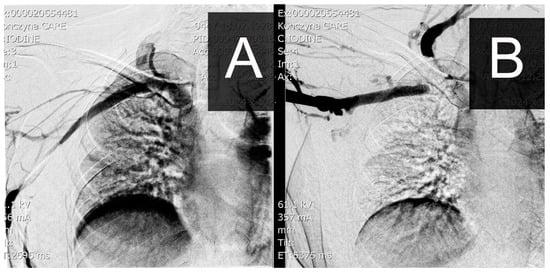

The second option is a functional but invasive phlebographic examination, which requires access to the peripheral veins of the examined limb and the administration of a contrast agent under diagnostic conditions. During examination, the standard anatomical positioning of the limb and abduction up to 90 degrees are used. In a venographic image, you can similarly obtain an image of stenosis or complete occlusion, as shown in Figure 3.

Figure 3. Image of a venographic examination at rest (A) and with the limb abducted to 90 degrees (B) with occlusion at the level of the clavicle/1st rib.